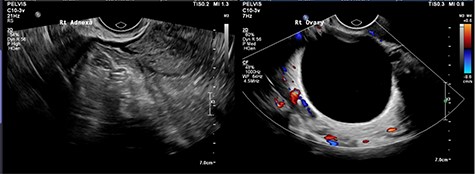

CT abdomen showed two cystic structures in the pelvis, and follow-up ultrasound demonstrated a 5.8-cm unilocular simple cyst contained within the right ovary, and a 3-cm left tubo-ovarian complex with associated hydrosalpinx (Figs 1–3).

Ultrasound imaging of the right ovary, demonstrating a simple cyst.

Trans-vaginal ultrasound is the gold standard modality for characterizing an adnexal mass, though para-tubal cysts and ovarian cysts can be difficult to distinguish [2, 4]. Unfortunately, the diagnosis of tubal torsion is difficult to make with imaging [2]. Arterial and venous flow to an adnexal mass may be demonstrated with colour Doppler, through the presence of flow does not exclude torsion [2]. The presence of sonographic features in conjunction with the patient’s symptoms should guide the need for diagnostic surgery.